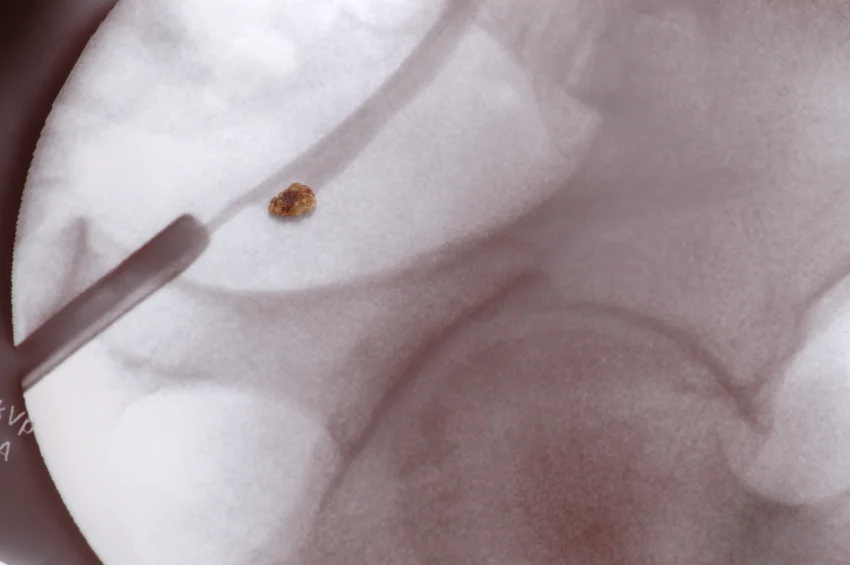

Read MoreLet’s face it – all of us have heard of kidney stones or maybe have even experienced them. But bladder stones? Yes, stones can form in the bladder. They are much more common in men past the age of 50 but are much less common than kidney stones. If they are small enough they may cause no symptoms passing on out the body on their own without a person even knowing they had any. But, unfortunately, more often than not, they will make their appearance known causing pain or other problems on urination.

Read MoreBladder stones are crystalline masses that are developed from the minerals and proteins found in urine.

Read MoreIf you've had kidney stones, you know the immense pain they cause. Kidney stones are small, hard deposits, typically composed of mineral and acid salts that form inside your kidneys.